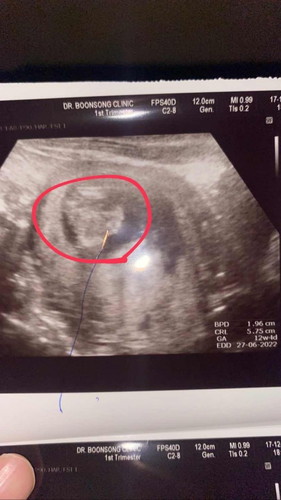

ผนังท้องไม่ปิด

แม่ๆบ้านไหน ที่ผนังหน้าท้องลูกไม่ปิดบ้างค่ะ อยากรู้ประสบการ เป็นยังไงกันค่ะ ช่วยแชร์ให้ทีนะค่ะ ขอบคุนค่ะ